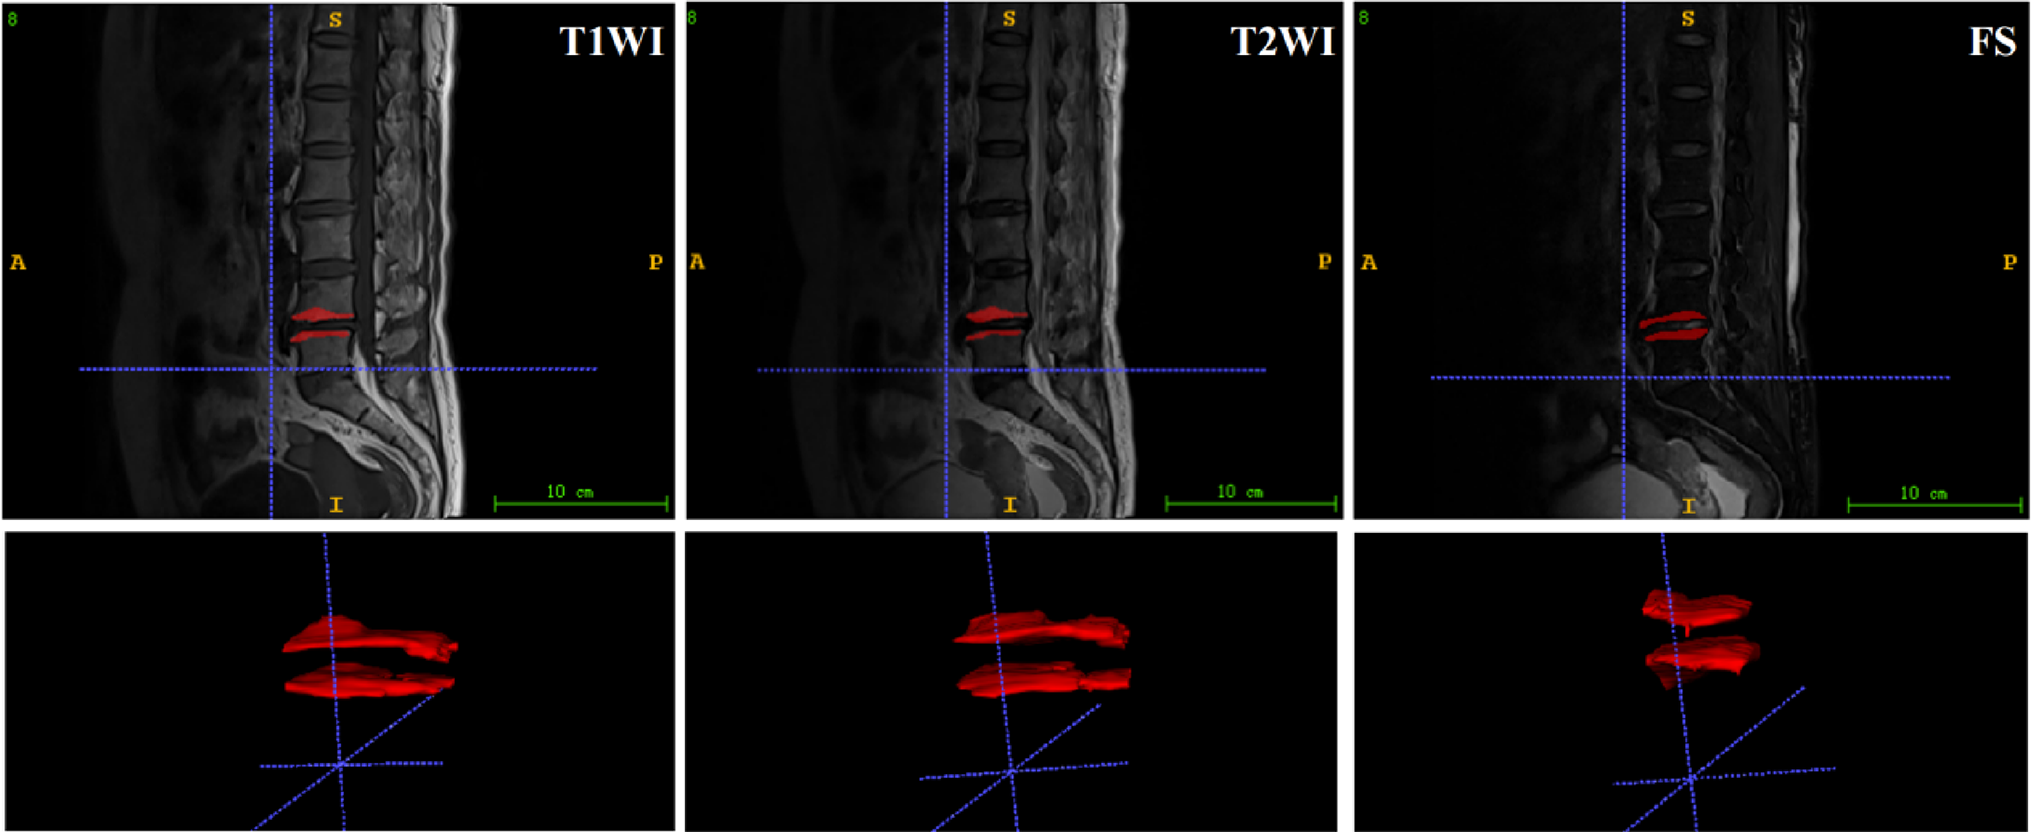

Unilateral lumbar paraspinal muscle degeneration is not sufficient to drive spinal deformity in mice

Paraspinal muscle degeneration and dysfunction are commonly observed in patients with adult spinal deformity, though their...

European Spine Journal